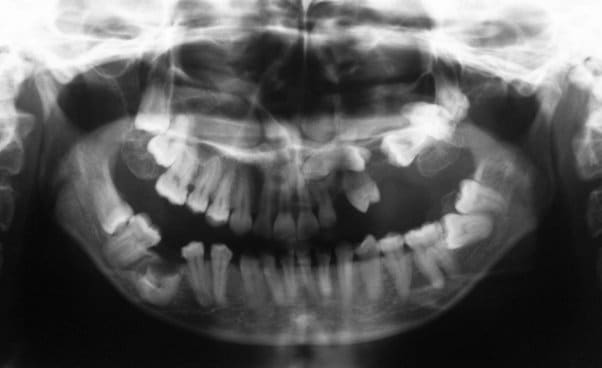

SI joint les photo intra buccal pre traitement et pendant traitement.

Comment expliquer vous le développement ce canting en frontal et de l'open bite en Postérieur ?

Qu'elle est la source du mal ?

Les radio devraient aider un peut mais les photos sont suffisante encore une fois.

Il y a ma connaissance une seul chose qui peut expliquer comment passer de la situation 1 a la situation 2.

Il y avait ankylose de la 22 mais pas des molaires.

Sa se devine ici car le fil est quasiment droit ce qui signifie que sa forme c'est exprimé presque complètement.

Le problème étant que si la forme du fil est correct sa position ne l'est pas.

La 22 étant ankylosé elle a fonctionné comme un point d’appui et a fait bouger tout le reste.

Dans ce cas c'est impressionnant car la dent ankylosé

- était mal positionné en début de traitement

- Qu'il n'y avait aucun dent dans le secteur postérieur pour limiter les effet.

Le fil rond pouvait tourner dans le slot de 22, vue qu'il n'y avait pas de dent en postérieure rien n’empêchait la rotation du fil et donc l’aggravation de la malocclusion.

La 21 qui était proche a était la plus affecté sa se voit bien sur les photo avec bracket, elle a subit une importante rotation dans le sens mesio distal et a était procliner. Son changement de position a eu un impacte sur 21 puis sur 11 ect ect , les effets devenant de plus en plus faible a mesure que l'on s'éloigne.

On a eu une important proclination de l'ensemble des incisive.

Mais encore une fois ce qu'il faut noter c'est le changement important au niveau de 21 avec un FIL PARFAITEMENT DROIT au niveau des incisives

Le dernier cas de ce type que j'ai vue était du a une ankylose de 32 mais vue que les arcades sup et inf était compléte les effet était plus modeste. La 32 était disto versé est avait entrainer une extrusion de 31 et 41 comme d’habitude le schéma était fil quasi droit mais dent qui ne sont pas en bonne position.

Pour savoir ou se situe le problème il y a une règle simple

avec un fil continue vous pouvez facilement réaliser des extrusion mais une intrusion est impossible. Donc pour savoir ou est la dent causal vous chercher la dent qui est en bout de chaîne du groupe de dent ayant subit une extrusion. Le senior qui suivait le cas pensait que la 22 avait subit une intrusion ce qui est une impossibilité biomécanique. La dent qui semble avoir subit une intrusion n'a en fait pas bouger mais a causer l'extrusion de tout le rest, i.e. elle est ankylosée.

La prof responsable c'était fait critiquer sur deux points :

- le fait de ne pas avoir penser a l'ankylose malgré les antécédent de la patiente ( voir radio )

- avoir utiliser une mécanique straight wire sur une arcade incomplète. Même si aucune dent n'est ankylosés les résultat peuvent être incertain vue cette mécanique a était développer pour une arcade complète, donc avec un effet stabilisateur des deux secteur postérieure.